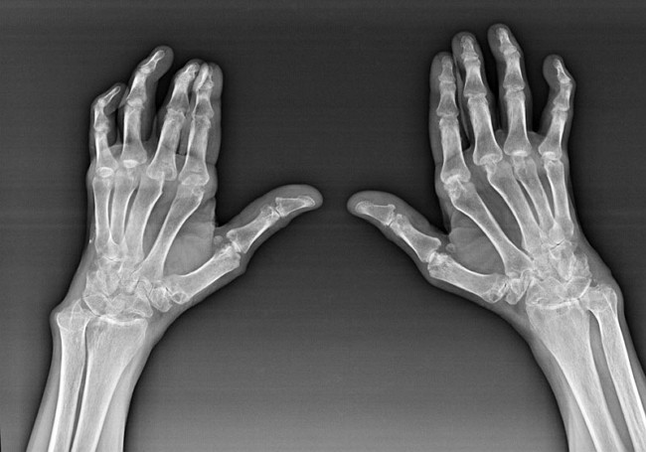

Rheumatoid arthritis

Rheumatoid arthritis is a disease in which the human immune system damages body tissues.In other words, rheumatoid arthritis is an autoimmune pathology.This disease is also systemic, since many tissues are affected (muscles, joints, vases, etc.) and organs (Heart, kidneys, lungs, etc.) in the body.

Despite the fact that rheumatoid arthritis is a systemic disease to a greater extent, the joints suffer, while the injury of other tissues and organs is in the background.With this disease, almost all types of brushes can be influenced (Drawings from wrist, carpal dangers, metacarpal-falan joints, inter-falan).The lesion is generally symmetrical (those.The same joints are interested) on both hands, accompanied by swelling, pain in damaged joints.In the morning, during the lifting from the bed, there is a little rigidity in the affected joints, which can last about 1 hour and then disappear without trace.

Quite often with rheumatic arthritis near the affected joints of the brush (More often the articop-falan joints, interfaces) Rheumatoid nodules appear.They are a rounded formation located under the skin.On the brush, these formations arise more often on the back.On palpation, they are dense, inactive, painless.The number of them can vary.